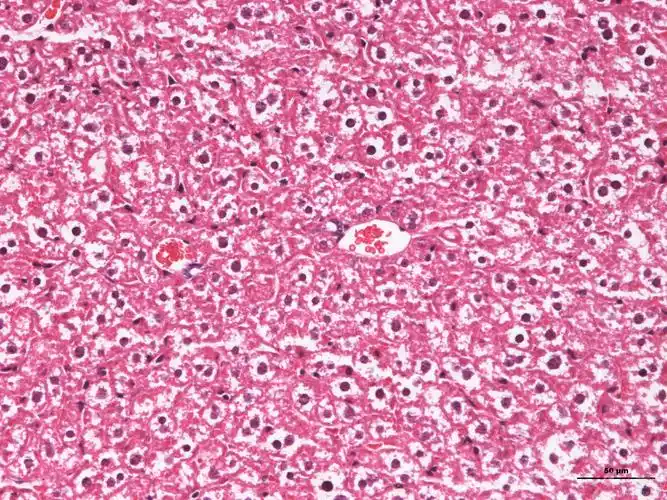

小鼠肝脏切片:深染的胞核是肝细胞核,还是肿瘤肝转移的?

【求助】小鼠正常肝脏he 染色图片

小鼠肝h&e染色图片,这些白色是脂肪变性或细胞肿胀吗?

关于小鼠肝脏病理切片的请教